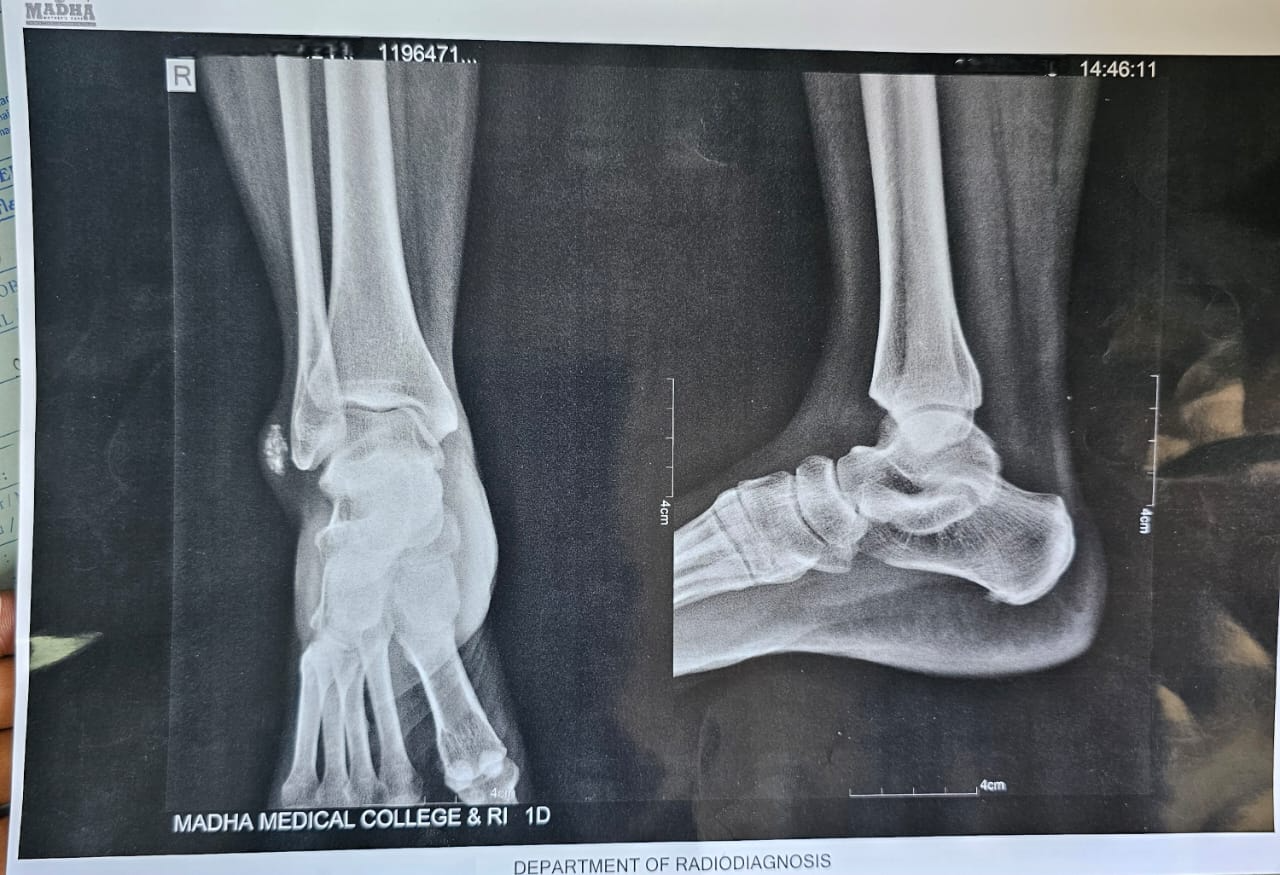

X-rays of the ankle showed a soft tissue bulge near the lateral malleolus, with a few punctate calcific specks – nothing extensive, but enough to suggest loose bodies (Fig. 2). Blood investigations were within normal limits. Based on the location and appearance, SC was kept high on the list. An MRI was done for further clarity. It picked up a subcutaneous swelling with internal areas of low signal, likely calcified, measuring around 2.1 × 0.6 × 1.5 cm, and sitting right over the lateral malleolus. The findings aligned well with what we suspected clinically.

Figure 2: X-ray showing soft tissue bulge near the lateral malleolus, with a few punctate calcific specks.